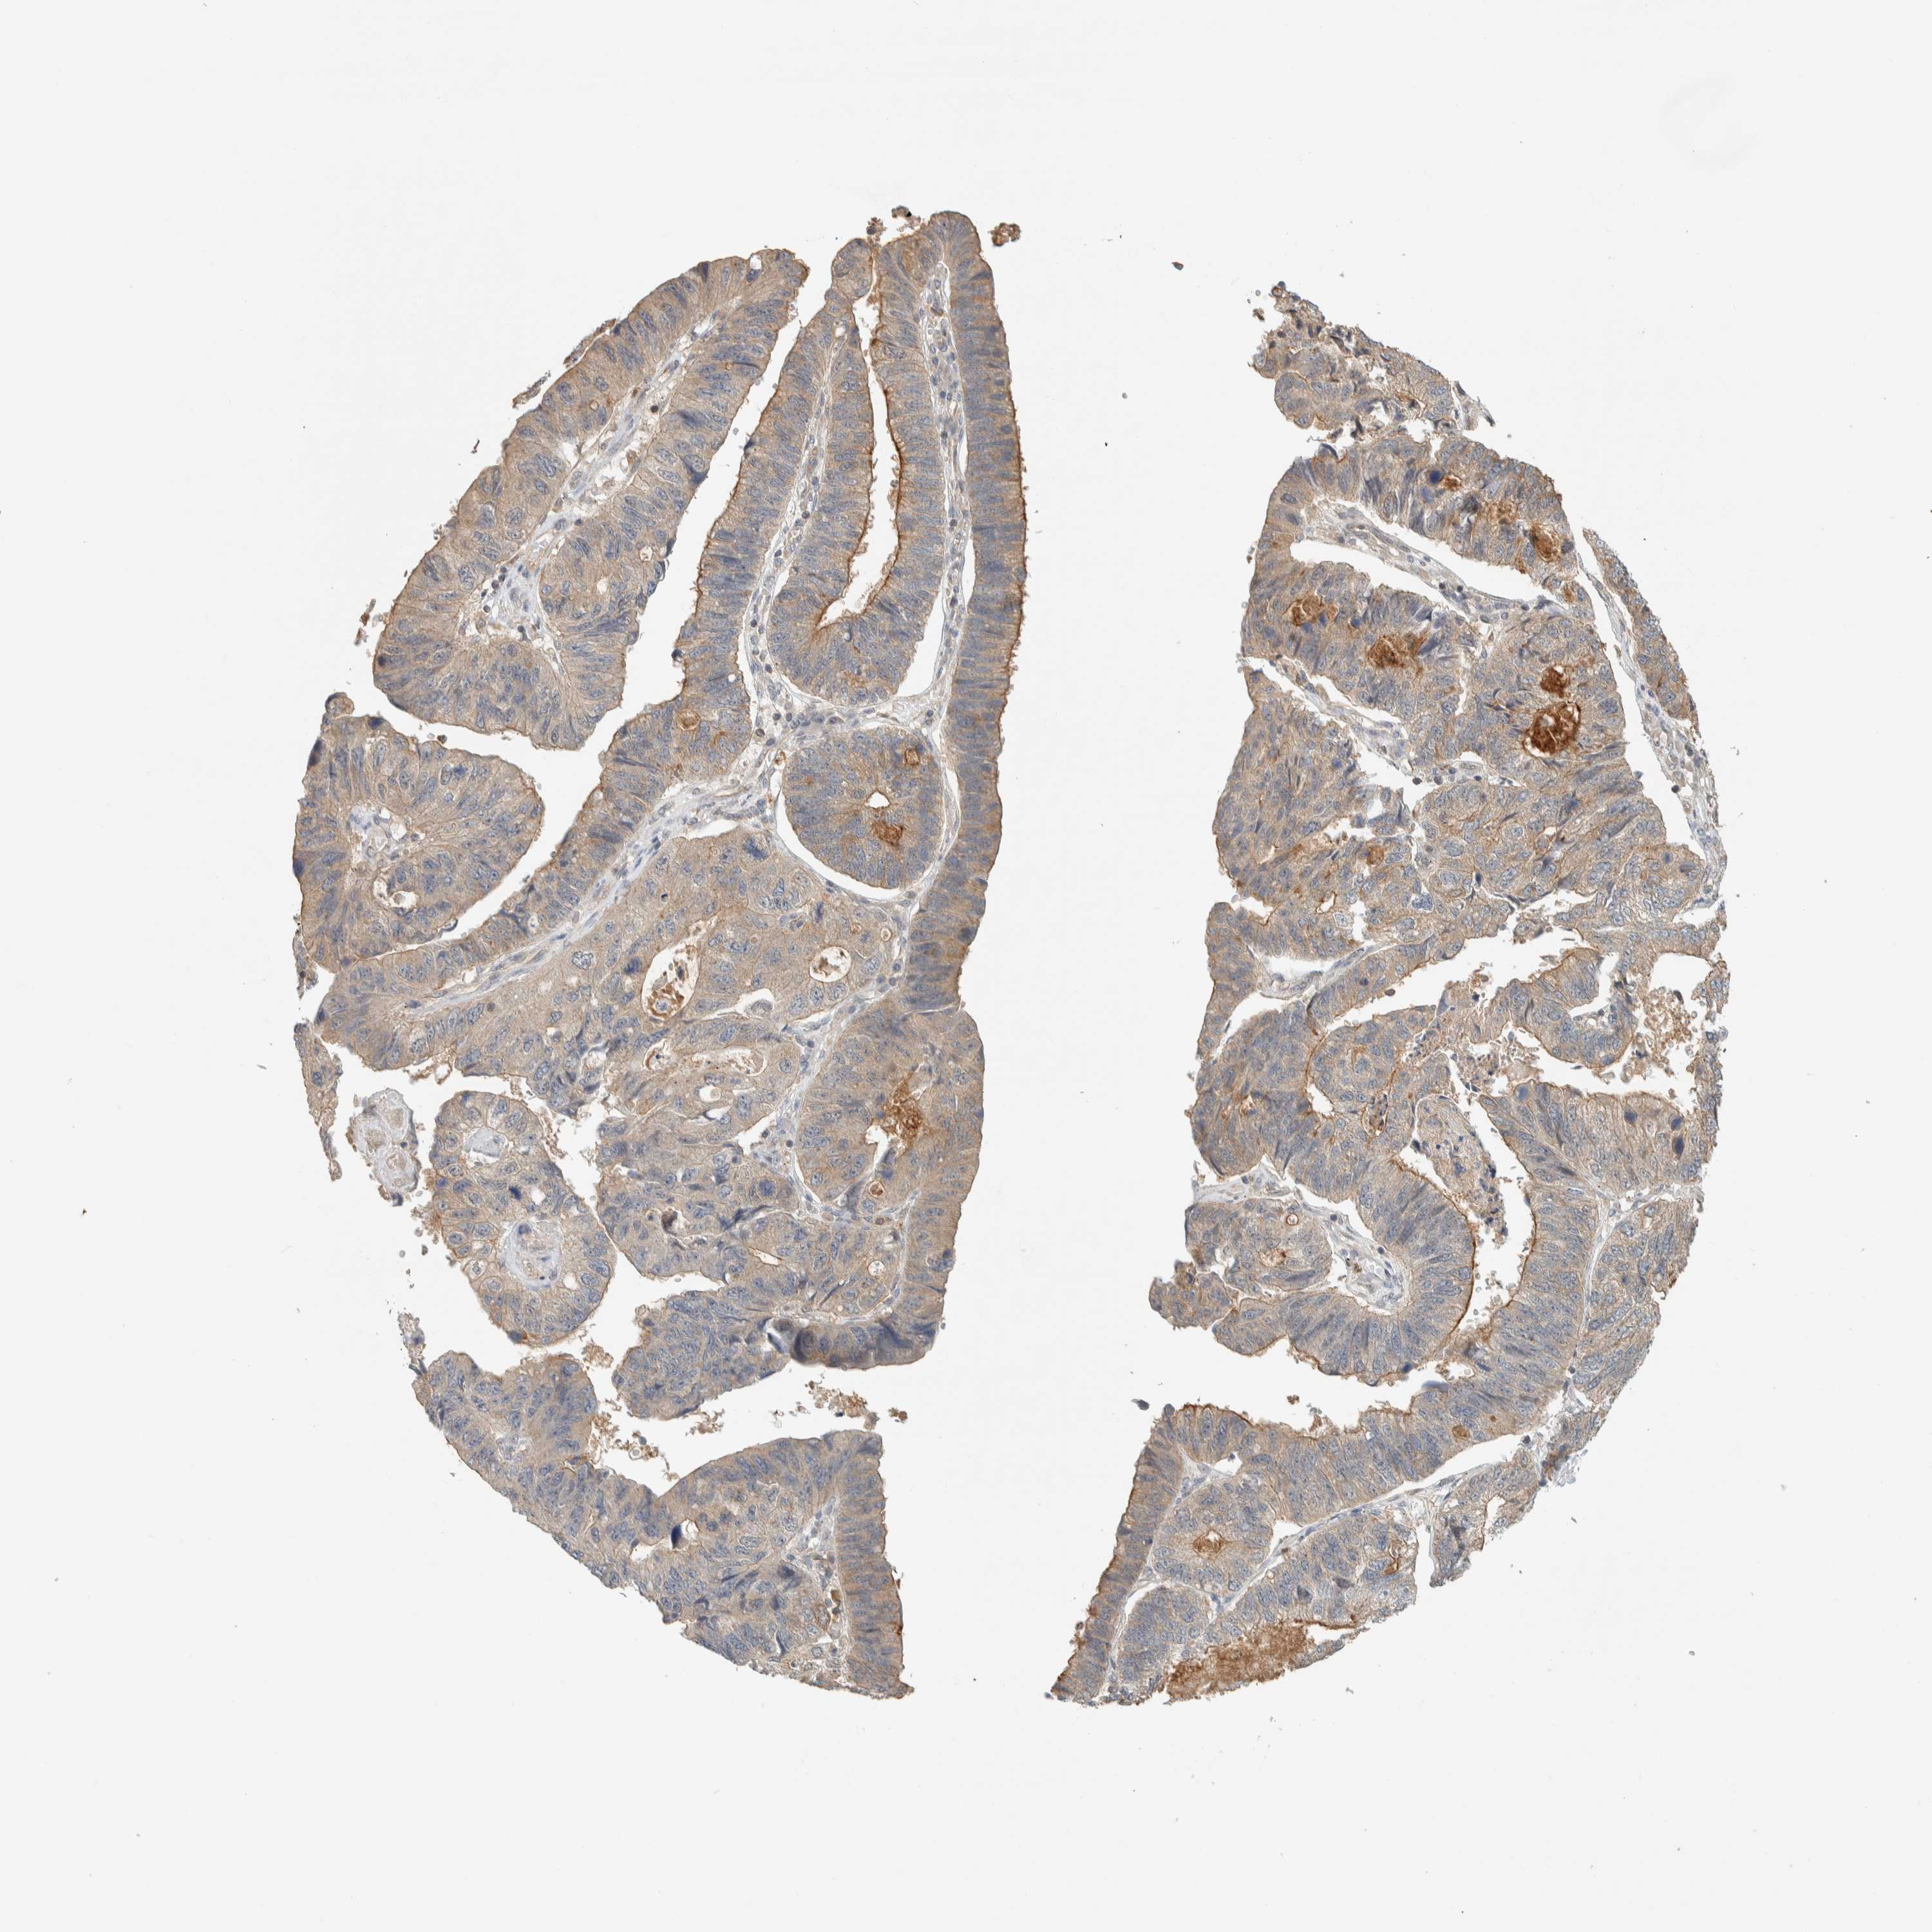

STOMACH CANCER - Protein expressioni

A mouse-over function shows sample information and annotation data. Click on an image to view it in a full screen mode. Samples can be filtered based on level of antibody staining by selecting one or several of the following categories: high, medium, low and not detected. The assay and annotation is described here.

Note that samples used for immunohistochemistry by the Human Protein Atlas do not correspond to samples in the TCGA dataset.

Antibody stainingi

Antibody staining in the annotated cell types in the current human tissue is reported as not detected, low, medium, or high, based on conventional immunohistochemistry profiling in selected tissues. This score is based on the combination of the staining intensity and fraction of stained cells.

Each image is clickable and will lead to virtual microscopy that enables deeper exploration of all samples and also displays staining intensity scores, fraction scores and subcellular localization as well as patient and tissue information for each sample.

Antibody HPA023904

Antibody HPA024010

Antibody HPA025960

Antibody CAB017037

Staining

High

Medium

Low

Not detected

Intensity

Strong

Moderate

Weak

Negative

Quantity

>75%

75%-25%

<25%

None

Location

Nuclear

Cytoplasmic/membranous

Cytoplasmic/membranous,nuclear

Adenocarcinoma, NOS